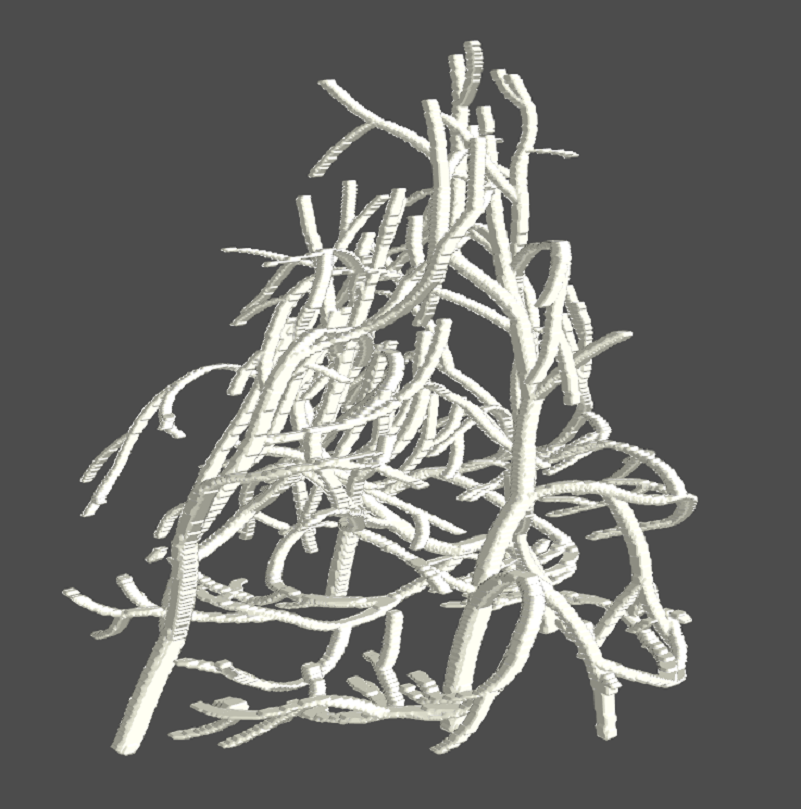

Our method is based on the theory of persistent homology [20], which extracts 1D (loops) and 2D (bubbles) topological structures with guaranteed robustness [14]. These structures correspond to curvilinear tissue structures (e.g., ducts, vessels, etc.) and voids enclosed by tissues and glands in their proximity. As shown in Fig. 2, compared to previous radiomics features, the topological structures provide a much richer structural context for the modeling of tumor microenvironment. Since these structures are extracted in an unsupervised manner, the quality of their interpretation becomes a key consideration. Using a phantom breast imaging dataset (VICTRE [5]), we validate both quantitatively and qualitatively that these topological structures are reasonable approximations of the breast tissue structures. As illustrated in Fig. 1, the extracted topological structures delineate the glandular tissues of a phantom breast image.

We first compute salient topological structures from the input image utilizing persistent homology theory. Topological structures of dimensions 1 and 2, i.e., loops and bubbles, can both correspond to important tissue structures. 1D topological structures capture curvilinear structures such as ducts, vessels, etc. 2D topological structures represent voids enclosed by the tissue structures and their attached glands. These topological structures directly delineate the critical tissue structures with high biological relevance. Thus we hypothesize that by focusing on these tissue structures and their affinities, we can gain pertinent contextual information for pCR prediction.

2.2 Persistence Cycles and Their Computation

Although the persistence diagram has been used for topological analysis in various dataset [27, 74, 78], it only records limited information, i.e., the times at which these topological structures appear/disappear. We hypothesize that a detailed geometric realization of these topological structures can be crucial for learning from images. To this end, we propose extracting these topological structures and integrating them into the learning process. As shown in Fig. 3, we extract loops (blue) to denote 1D topological structures and bubbles (red) for 2D topological structures. These structures are then used to guide the attention mechanism within the neural network.

We show that the extracted topological structures effectively capture the breast tissues. We apply our method introduced in Section 2.2 to the synthetic MRIs to extract topological structures, and then compare these extracted structures with the ground truth tissue in the synthetic volumes. If there is a significant overlap, it indicates that the extracted topological structures closely approximate the actual breast tissue. In our study, breast tissue is defined as the union of all tissue types characterized by rich structures, including glandular tissue, TDLU, ducts, arteries, and veins. Conversely, fat, skin, nipple, muscle, and ligament are categorized separately from breast tissue and are considered as background elements.

Qualitative validation. Figure 6 illustrates how topological structures effectively capture breast tissues. The first row presents 3D renderings of VICTRE-generated synthetic breast phantoms for four distinct profiles. The second and third rows display two slices at different positions of the corresponding breast phantoms, where the topological mask (in blue) and ground truth breast tissues (in white) are shown, alongside the breast outlines (in red). It is important to note that each slice’s rendering includes several additional slices around the target cross sections for detailed examination. It is clear that the blue topological structures closely match the white breast tissues, especially noticeable in the scattered and fatty volumes. This observation highlights that our extracted topological masks effectively mirror the actual breast tissues, confirming the biological significance of these structures.